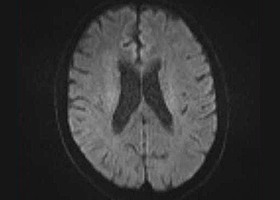

右側で頸部内頚動脈が細くなっているため右脳に脳梗塞を生じた患者様です。

術後MRI拡散強調画像

頸部狭窄は解消しており、新たな脳梗塞など生じていません。